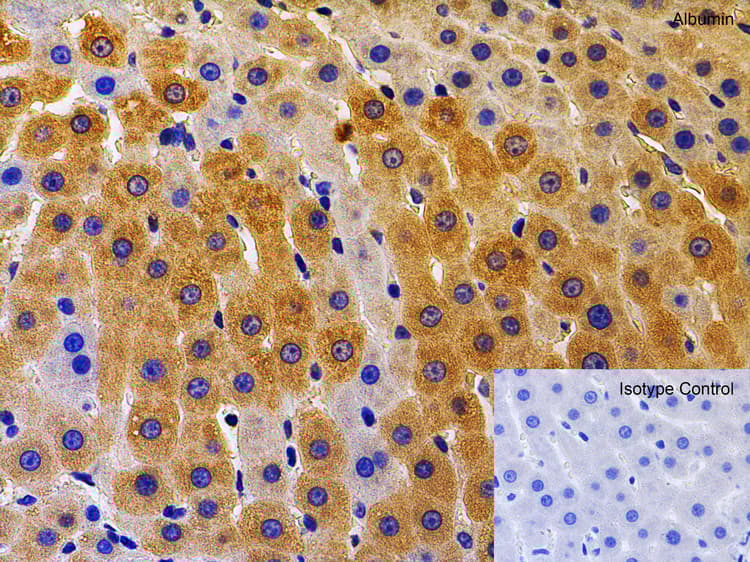

Chicken Polyclonal Albumin antibody. Suitable for WB, IF, IHC-P and reacts with Mouse, Rat, Human samples. Cited in 52 publications. Immunogen corresponding to Synthetic Peptide within Human Albumin.